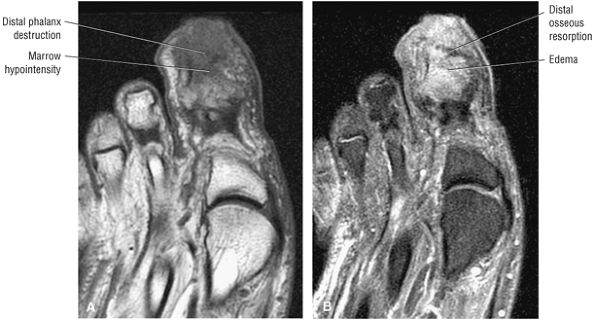

Thickening (Fig. 5.180) or absence of the ligament in acute injury

-

Subacute to chronic residual thickening in a healed and scarred ligament (Fig. 5.181)

Chronic instability associated with attenuated or hypoplastic ligament with sharper, more defined ligament margins